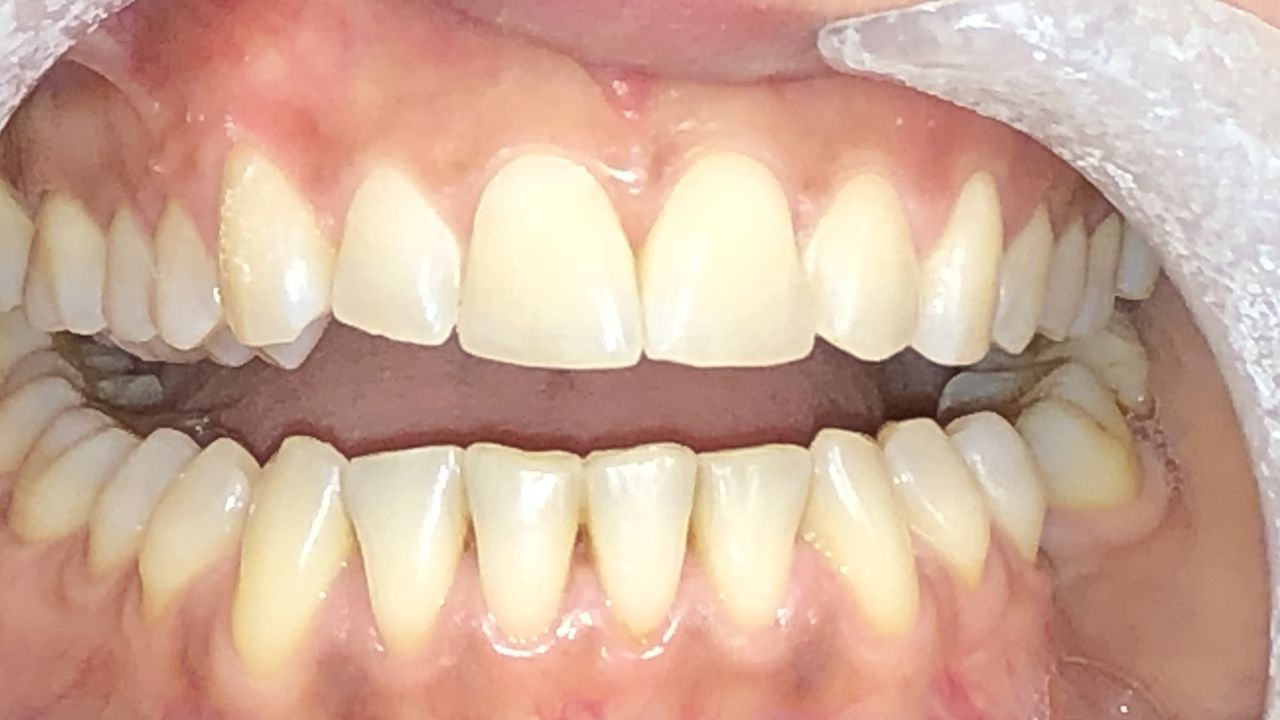

Foto e video

Il Dottor Luca Strazioso ha qualità rare; mi ha ascoltata attentamente sin dal primo appuntamento, con la sua pazienza, competenza e professionalità durante ogni seduta ha ricostruito il mio sorriso, mi ha ridato la sicurezza che ormai avevo perduto. Posso affermare di essere rinata grazie alle sue mani, alla sua intelligenza e sensibilità. Inoltre, la Signora Antonella, assistente alla poltrona, è assolutamente insostituibile e generosa. Infinitamente grata ad entrambi.